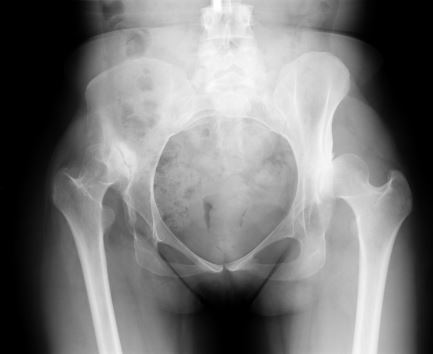

方法:在一项回顾性研究中,我们评估了24例非骨水泥全髋关节置换术的结果和并发症,共 24例(20例女性和4例男性)Crowe型IV型发育不良。采用非骨水泥全髋关节置换术结合转子下缩短截骨术,将髋臼假体放置在解剖学旋转中心的水平处。术后平均随访4.8年,对患者进行评估。

结果:平均的Harris髋关节评分从术前的 43 分提高到了最终随访时的 89 分(p <0.01)。 28 个髋中有12个(43%)发生了早期或晚期并发症或再次手术。28例转子下截骨术中有2例(7%)发生骨不连。有1例股骨柄松动,1个髋臼假体松动,1个髋臼内衬脱离。术后有4例髋关节脱位。在最后一次随访时,其余组件均固定良好。未发现坐骨神经损伤的病例。

结论:在髋关节发育不良继发高位髋关节脱位的患者中,非骨水泥全髋关节置换术结合股骨转子下缩短截骨术可以成功固定植入物和获得截骨部位愈合,平均术后Harris髋关节评分89分。 然而,这一类患者术后的并发症发生率显著高于骨关节炎的初次全髋关节置换术。